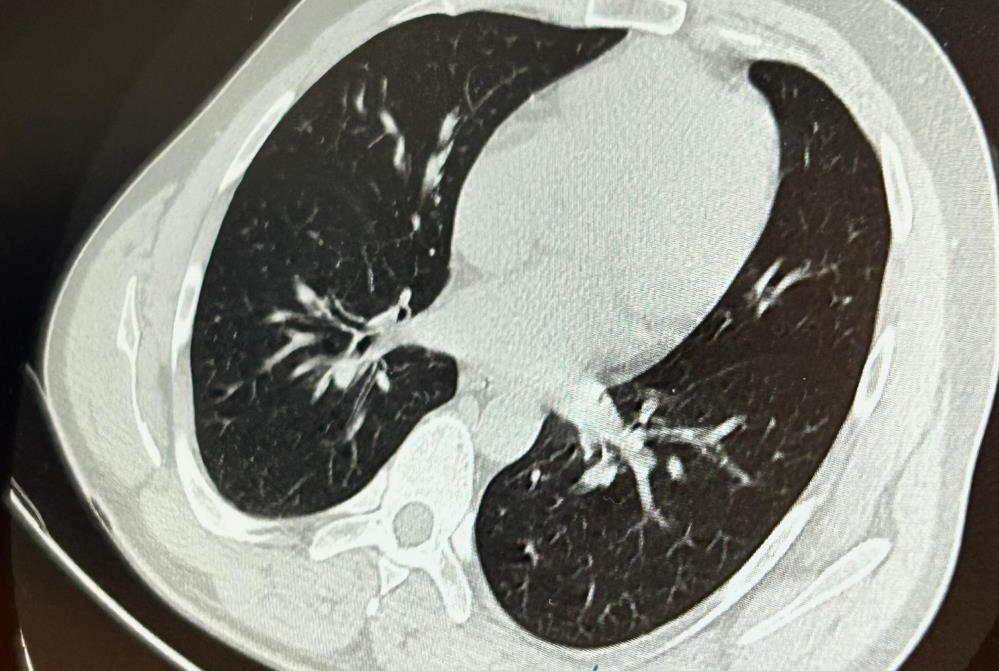

Van’ın İpekyolu ilçesinde ikamet eden F.T. isimli hasta, dış merkezli bir diş kliniğinde implant tedavisi gördüğü sırada, implant vidası yanlışlıkla soluk borusuna kaçtı. Nefes borusuna kaçan vida nedeniyle hasta, ileri tetkik ve tedavi amacıyla Van Eğitim ve Araştırma Hastanesi’ne sevk edildi.

Göğüs Cerrahisi uzmanları Dr. Sadullah Aksoy ve Dr. Beniz İrem Ersoy Şığva tarafından hastaya bronkoskopi işlemi uygulandı. Sol akciğerin üst lobunda saplanmış şekilde tespit edilen vida, vidalı yapısı ve bulunduğu konum nedeniyle güçlükle yerinden oynatılabildi. Yapılan uzun ve titiz müdahale sonrası vida yerinden çıkarılamasa da hasta bir süre sonra geçirdiği öksürükle birlikte implant vidasını midesine gönderdi. Vida, daha sonra doğal yollarla vücuttan atıldı.